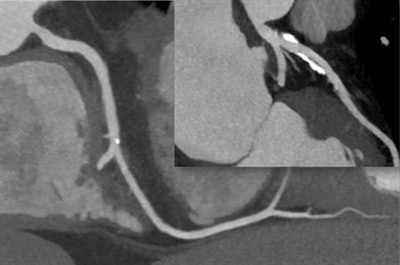

He acknowledged that CT was becoming an increasingly important diagnostic tool in cardiology, mainly because of its effectiveness in visualizing the coronary arteries and identifying stenoses in patients with acute or stable chest pain. But many patients have nothing wrong with their coronary arteries and still have chest pain, he pointed out.

"CT is particularly good at identifying those patients without stenosis who do not require further work-up. Effectively, showing that the coronary arteries are normal is the main value of CT," he said.

He stressed that by understanding the reasons for resistance, we can be better able to improve the situation. Highlighting the risk of false-positive results if CT is performed at poor image quality, Achenbach noted a patient whose scan generates a poor-quality CT might consequently undergo a substantial amount of downstream testing, which is unnecessary. Because CT is being used in a low-risk population generally, then it's vital to ensure the specificity is high, he said.

A typical false positive might arise where a patient actually has atherosclerosis on CT with calcifications, Achenbach explained. It might be interpreted as stenosis due to a poor-quality image.

"This is not good for the patient because they have some plaque but no stenosis," he noted. "However, using high-end technology and ensuring that the scan is acquired correctly can ensure in these difficult situations we can confidently rule out stenosis."